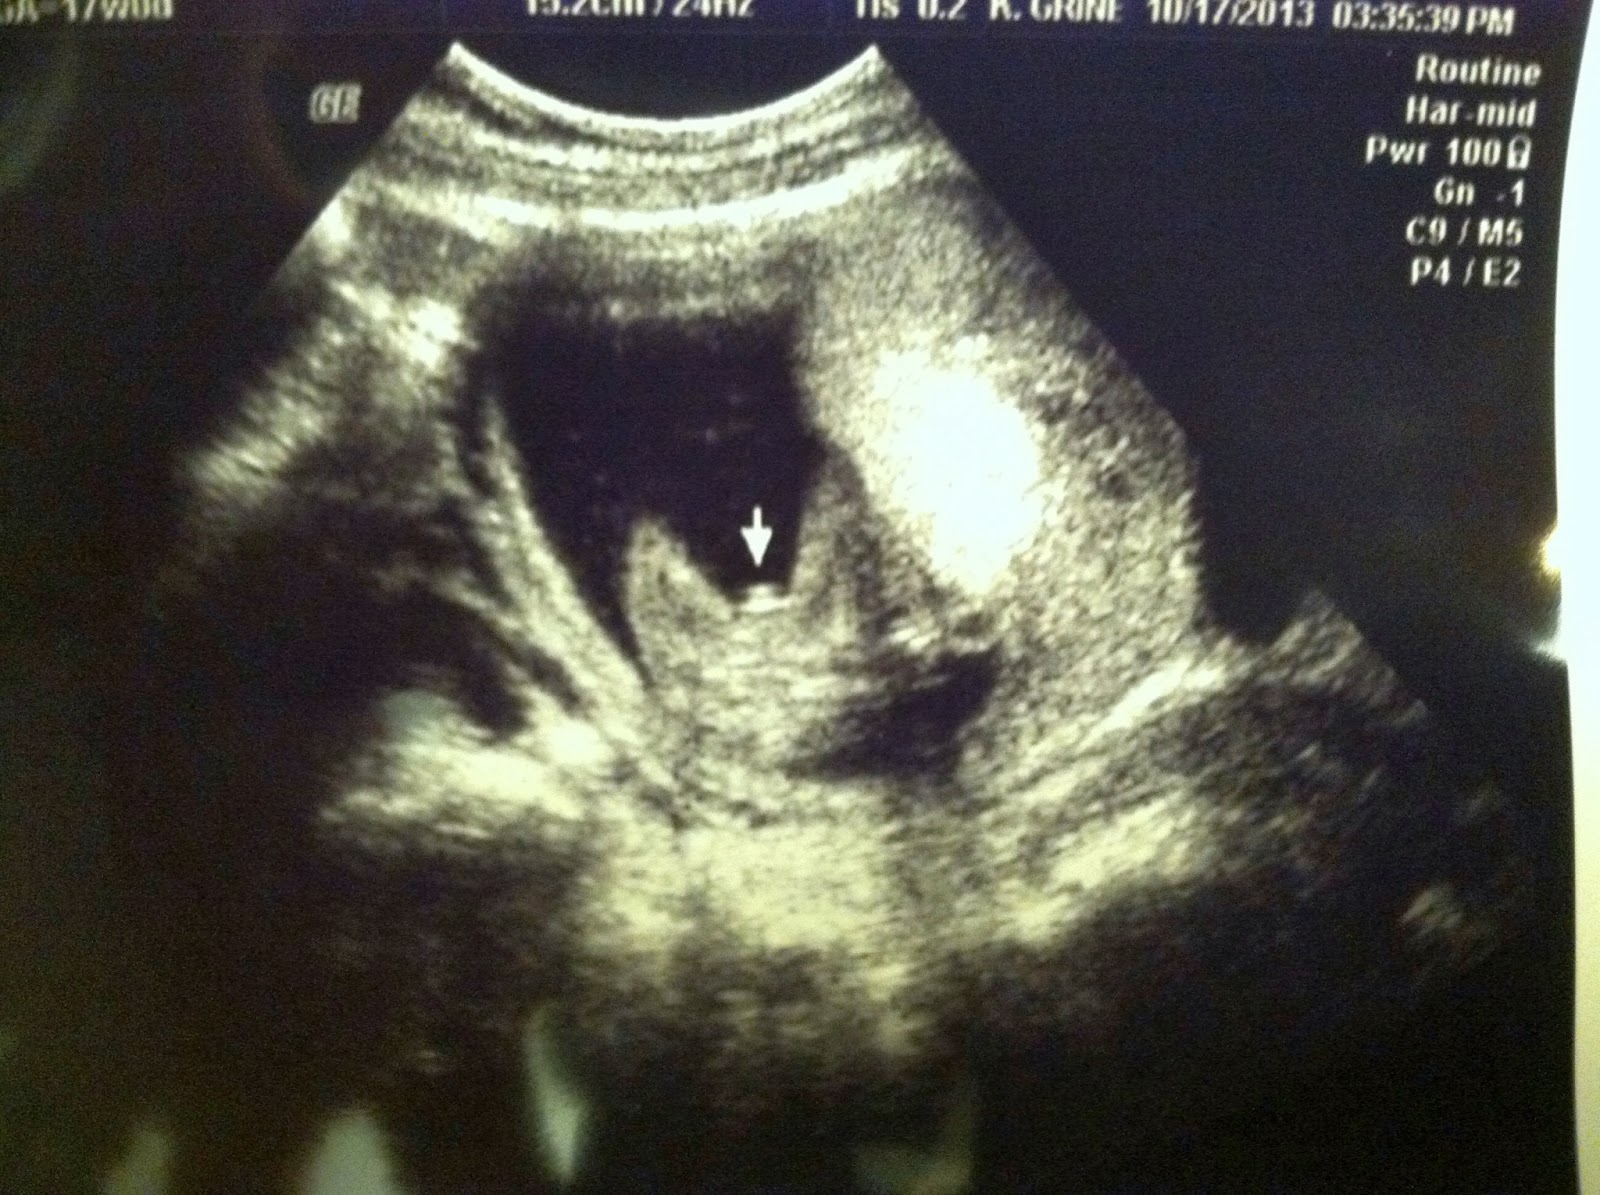

I went for my ultrasound on October 17 and they are 99% sure its a little boy!! The ultrasound tech's words exactly, "I am pretty sure that isn't going anywhere!"

We are so ecstatic to be having one of each. While I would have been tickled with another little girl, it would have been sweet for Norah Kate to have a sister... every daddy needs a son, and I would have been disappointed to Matt's sake. :)

Everything looked good on the ultrasound but I will get a more detailed anatomy scan for my 20 week visit in November. I can't wait to see him again!!